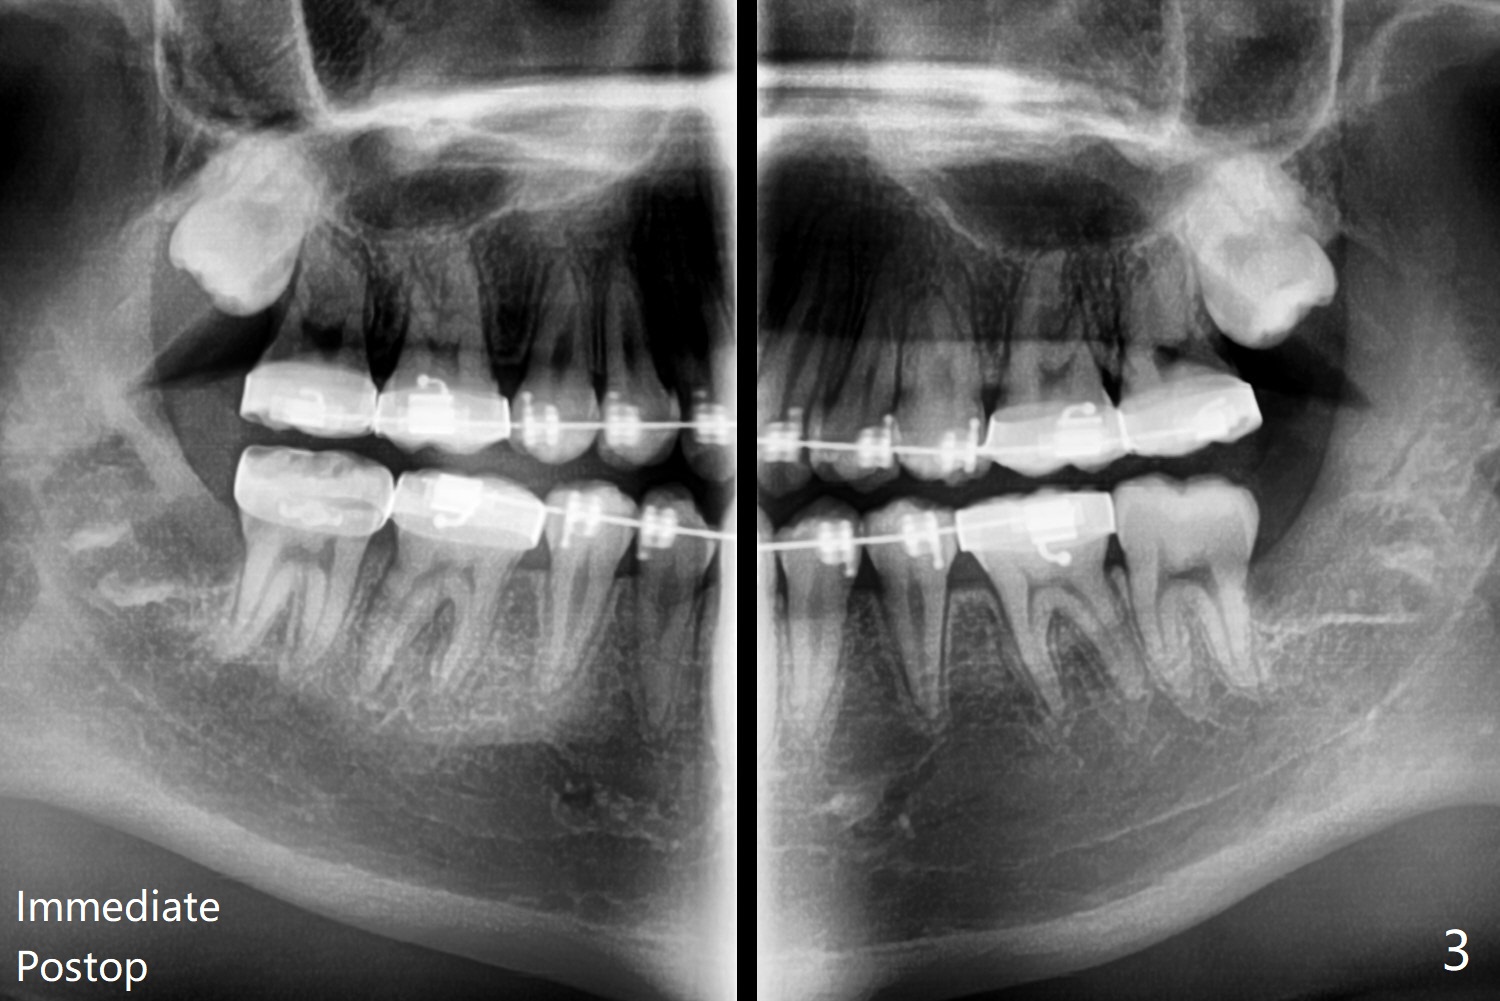

15岁男孩分离器使用后(图一:箭头)无法在左下7放置band,可能因为8阻生(图一,与图二对比)。1.5年后左下8萌出(图二),下颌8拔除,牙槽窝放置Osteogen Plug(图三),八个月后牙槽窝愈合(图四)。